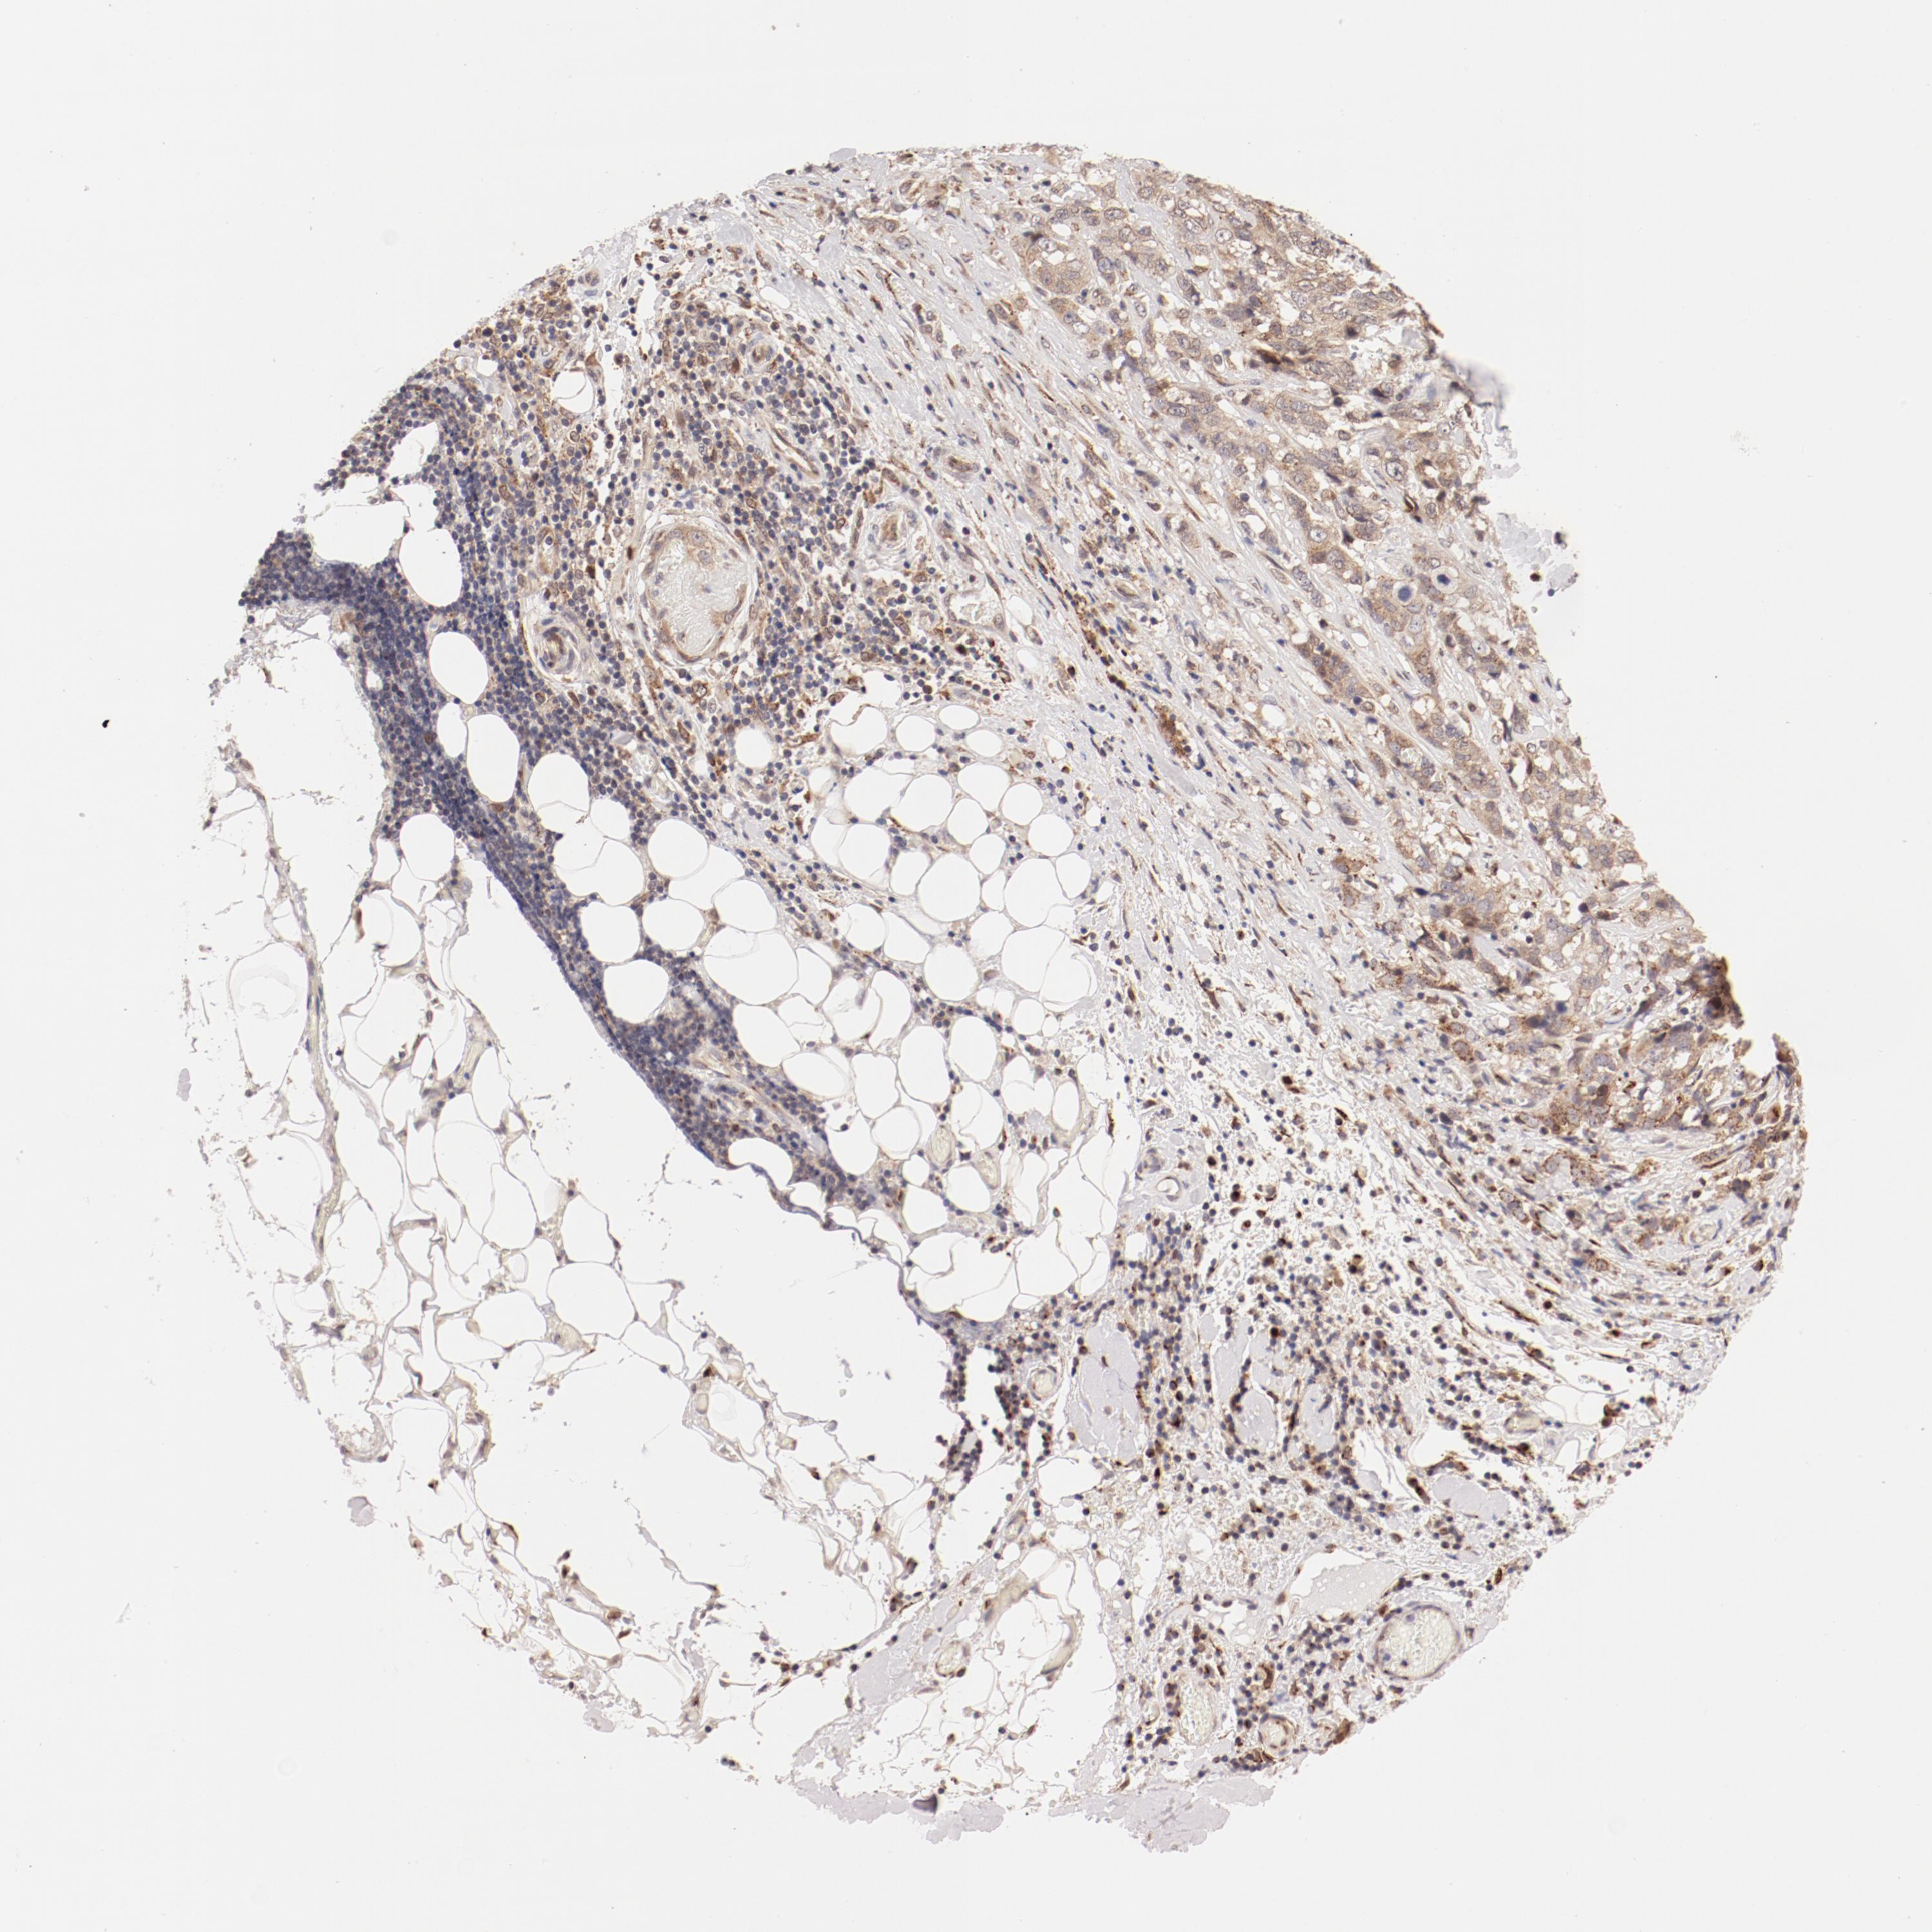

STOMACH CANCER - Protein expressioni

A mouse-over function shows sample information and annotation data. Click on an image to view it in a full screen mode. Samples can be filtered based on level of antibody staining by selecting one or several of the following categories: high, medium, low and not detected. The assay and annotation is described here.

Note that samples used for immunohistochemistry by the Human Protein Atlas do not correspond to samples in the TCGA dataset.

Antibody stainingi

Antibody staining in the annotated cell types in the current human tissue is reported as not detected, low, medium, or high, based on conventional immunohistochemistry profiling in selected tissues. This score is based on the combination of the staining intensity and fraction of stained cells.

Each image is clickable and will lead to virtual microscopy that enables deeper exploration of all samples and also displays staining intensity scores, fraction scores and subcellular localization as well as patient and tissue information for each sample.

Antibody HPA003403

Staining

High

Medium

Low

Not detected

Intensity

Strong

Moderate

Weak

Negative

Quantity

>75%

75%-25%

<25%

None

Location

Nuclear

Cytoplasmic/membranous

Cytoplasmic/membranous,nuclear

Adenocarcinoma, NOS

Adenocarcinoma, High grade